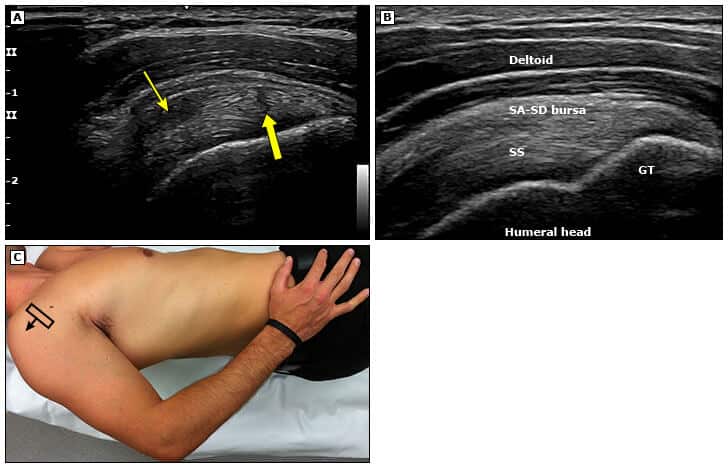

Realização do exame de ultrassom

A visualização adequada dos tendões exige um bom posicionamento do paciente (posição de Crass) e do transdutor, ajustes corretos no equipamento de ultrassom e manobras dinâmicas para obter as melhores imagens.

Para a maioria dos casos, utiliza-se um transdutor linear com frequência de 10 MHz e zona focal de cerca de 2 cm de profundidade.

A posição de Crass ideal, por sua vez, pode ser difícil em pacientes com dor, mas é possível facilitar a manutenção dessa posição pedindo ao paciente para simular o ato de pegar uma carteira no bolso de trás e sentar-se sobre a mão, utilizando o peso corporal.

Após posicionar corretamente o transdutor, o examinador pode realizar ajustes adequados na posição para melhorar a visualização do tendão e avaliar a anisotropia.